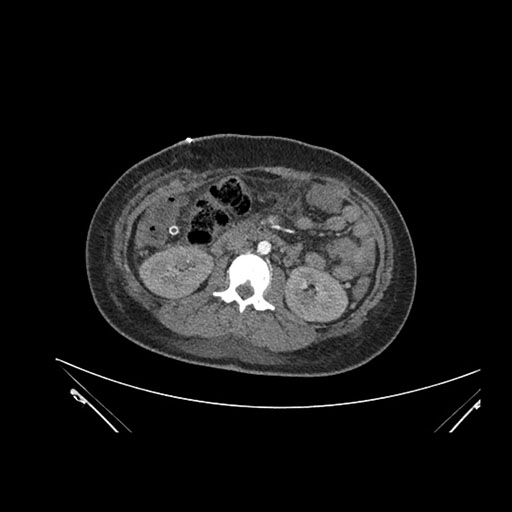

Imaging Analysis

Look through the patient's CT scan to identify any areas of concern for the necessary procedure.

Axial Venous